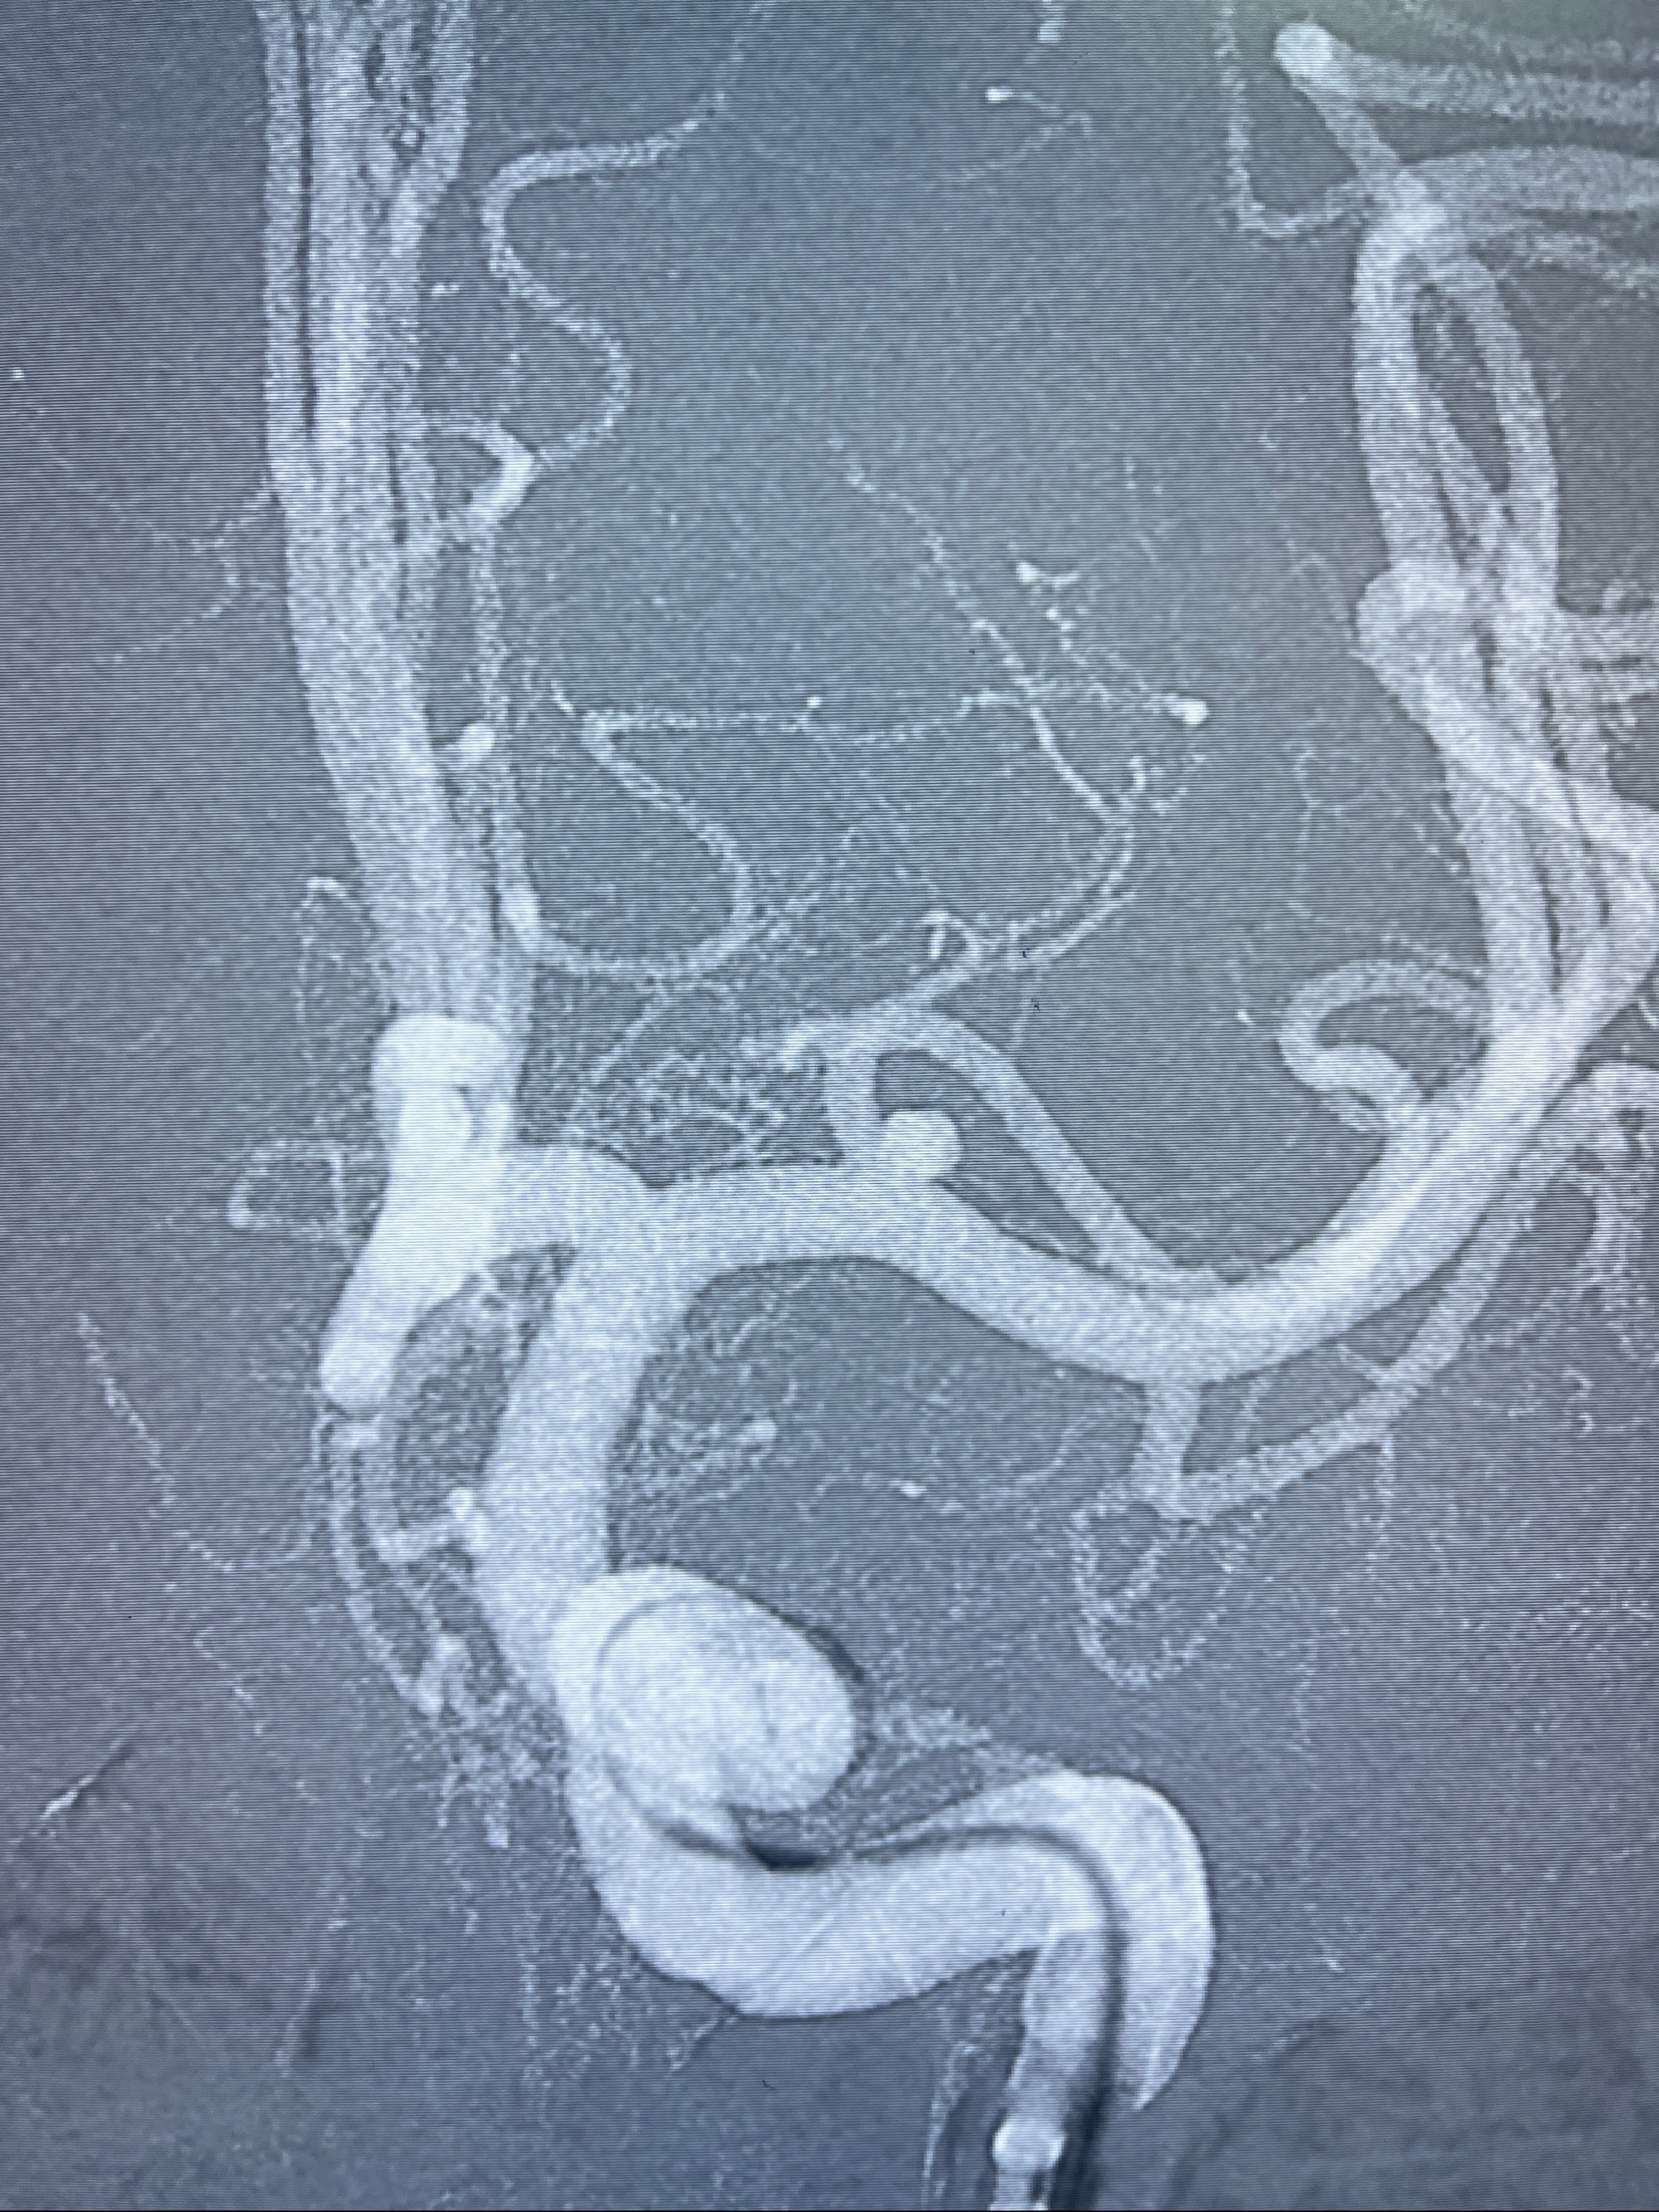

2023-08-14DSA:

左侧大脑中动脉动脉瘤,约2.6-2.8-3.4-2mm大小(瘤颈部、瘤体部、瘤高)